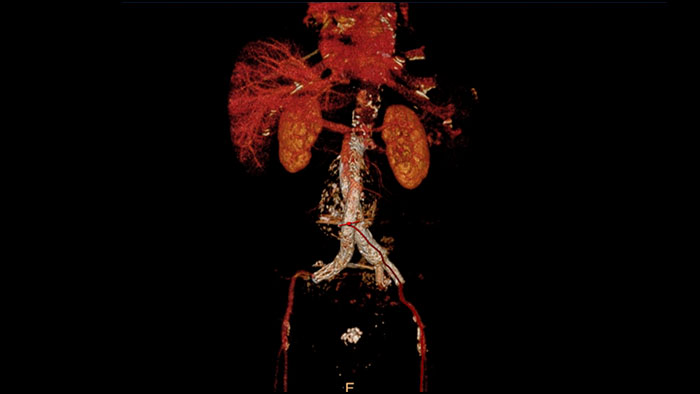

Advanced Vessel Analysis (AVA)

Multi Modality Advanced Vessel Analysis (AVA)

Comprehensive vascular analysis planning

Designed to examine and quantify different types of vascular lesions from CTA and MRA scans. It accommodates different modes of inspection, allows labeling different vascular lesions, and helps navigating through multiple findings.

Demonstrated to reduce the post-processing time by 50% when compared to manual Head & Neck CT angiography (CTA) analysis*.

advanced vessel analysis thumbnail

Benefits

• Ability to choose which Head & Neck Bone Removal method to be used (Standard vs. Smooth).

• Customizable Volume rendering “smoothness” for the 3D Head & Neck vascular structure using a smoothness control.

* Ardley N et al. Efficacy of a new post processing workflow for CTA head and neck. ECR 2013 / C-1760.